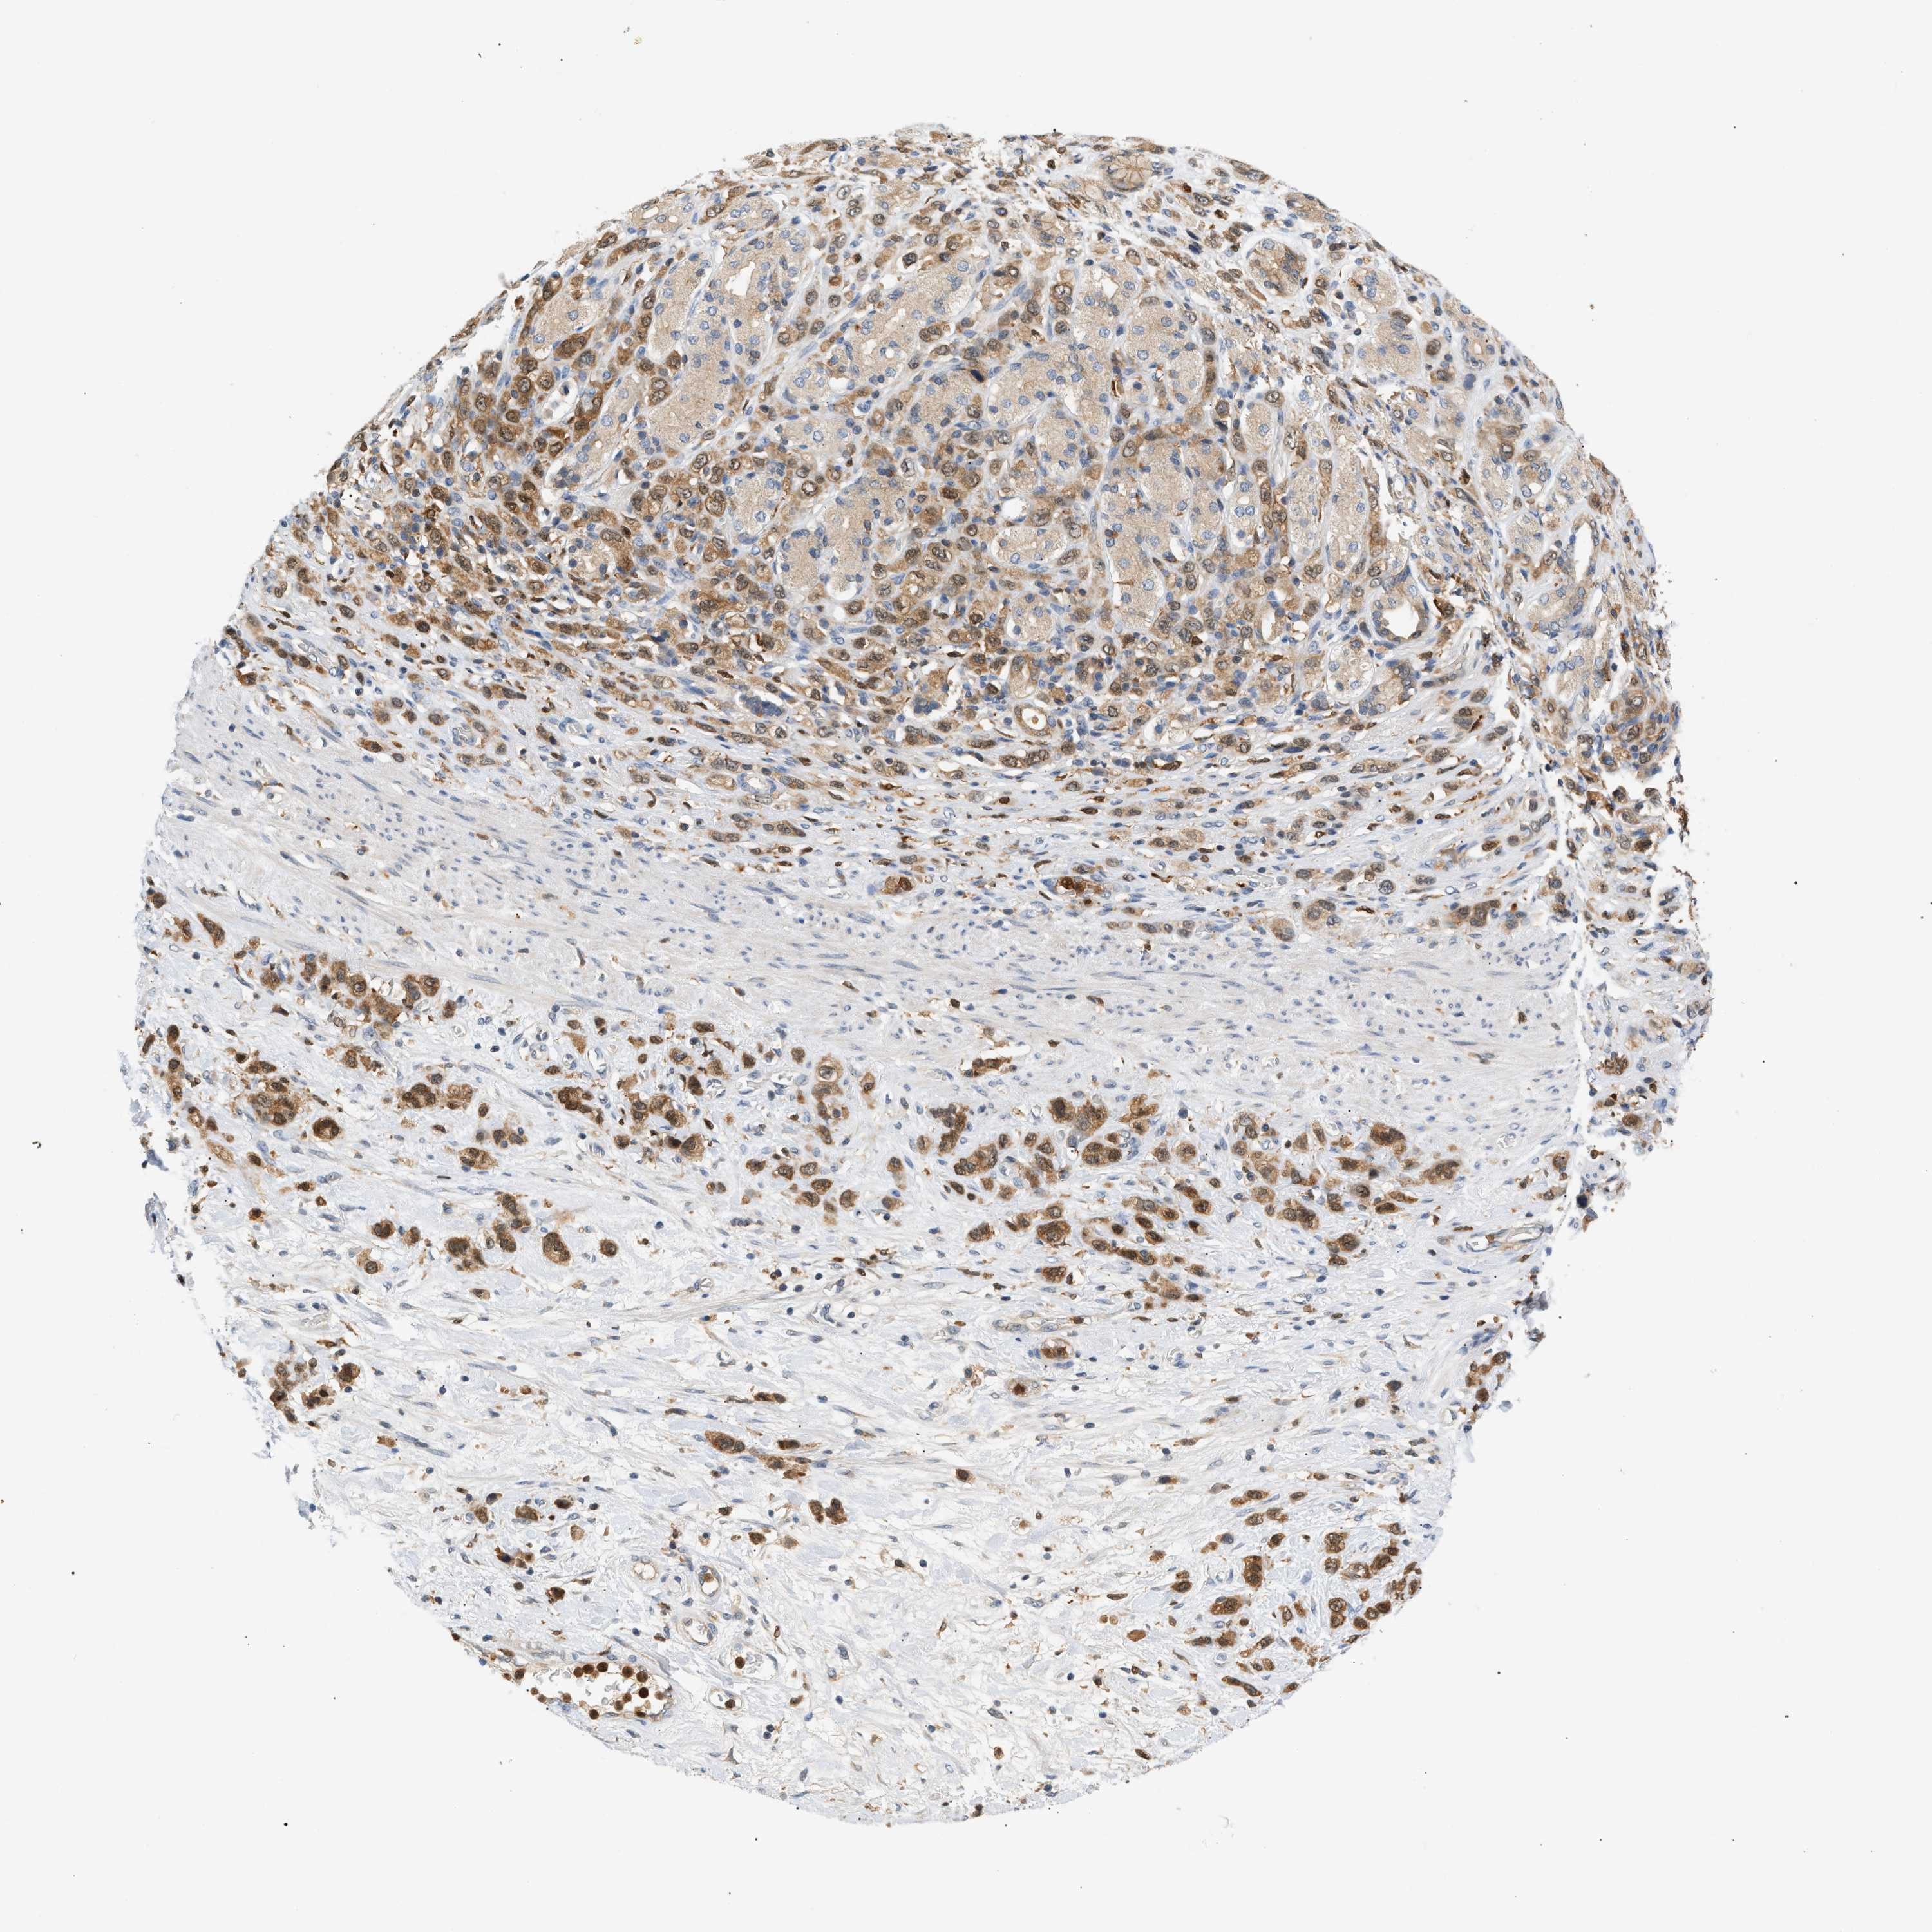

STOMACH CANCER - Protein expressioni

A mouse-over function shows sample information and annotation data. Click on an image to view it in a full screen mode. Samples can be filtered based on level of antibody staining by selecting one or several of the following categories: high, medium, low and not detected. The assay and annotation is described here.

Note that samples used for immunohistochemistry by the Human Protein Atlas do not correspond to samples in the TCGA dataset.

Antibody stainingi

Antibody staining in the annotated cell types in the current human tissue is reported as not detected, low, medium, or high, based on conventional immunohistochemistry profiling in selected tissues. This score is based on the combination of the staining intensity and fraction of stained cells.

Each image is clickable and will lead to virtual microscopy that enables deeper exploration of all samples and also displays staining intensity scores, fraction scores and subcellular localization as well as patient and tissue information for each sample.

Antibody HPA049074

Antibody HPA054496

Antibody CAB006853

Antibody CAB015948

Staining

High

Medium

Low

Not detected

Intensity

Strong

Moderate

Weak

Negative

Quantity

>75%

75%-25%

<25%

None

Location

Nuclear

Cytoplasmic/membranous

Cytoplasmic/membranous,nuclear

Adenocarcinoma, NOS

Adenocarcinoma, High grade